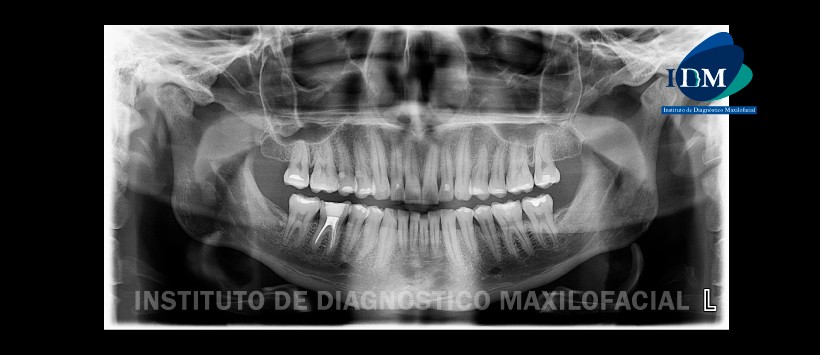

En la radiografía panorámica (Figura 1) se observa facetamiento y erosión bilateral de los contornos condilares; múltiples restauraciones y tratamiento de conductos en pieza 46.